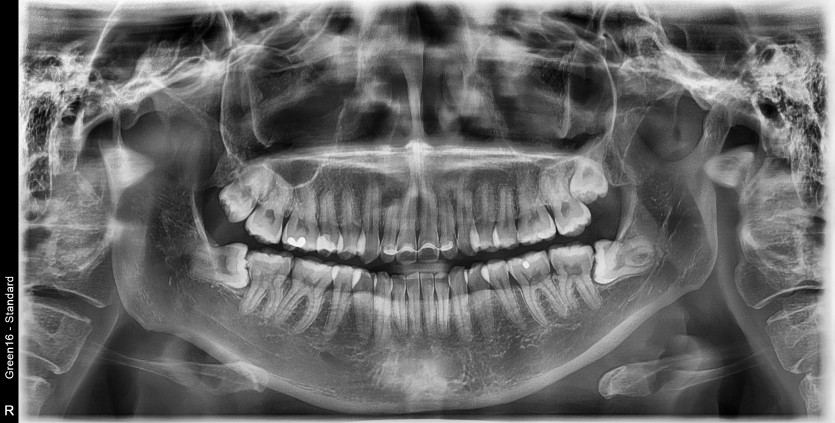

#18,38,48 사랑니 발치

구강 외과 전문의가 당일 발치했습니다.